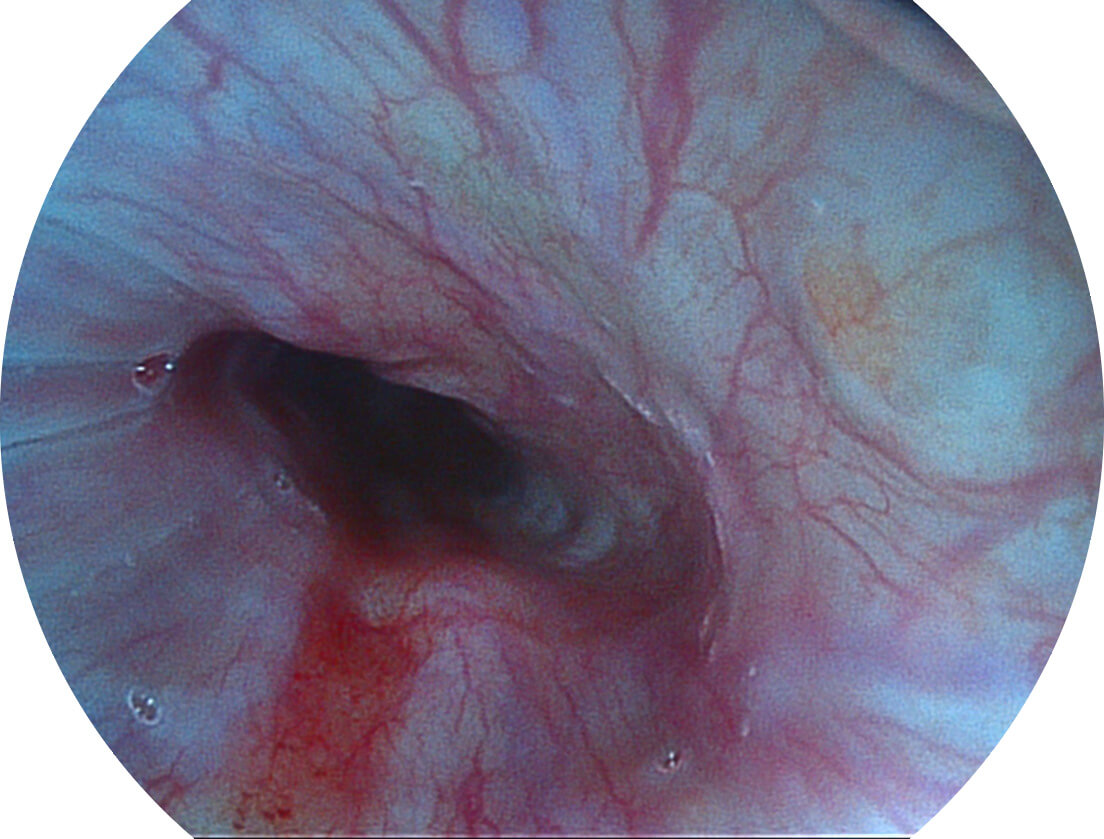

白光图像

SFI图像

采用光路合束技术,光谱自由度高,实现了更丰富的照明模式,染色模式SFI及VIST,从远景到近景,助力消化道早期疾病诊断。